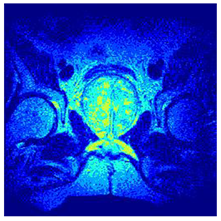

In this subsection, we will discuss the experiment designed to evaluate the performance of EO with cross-entropy for the segmentation of prostate MRI images. To this end, we use a group of reference images formed by a set of six prostate MRI images; see Figure 4. All the images from the group were extracted from the Ferenc Jolesz National Center for Image-Guided Therapy, Harvard Medical School, or Brigham Health Hospital datasets with no additional preprocessing [50]. Prostate MRI images are primarily used for disease diagnosis or to establish treatment for prostate-related diseases such as prostatitis, benign prostatic hyperplasia (BPH), and prostate cancer, among other diseases or medical conditions. In the context of this article, the images were used to test the efficiency of the equilibrium optimizing algorithm and compare it with the other six chosen algorithms. The segmentation of MRIs is carried out over four different thresholds levels: = 3, 4, 5, and 8. Due to the nature of the images, there was a limited number of different tissues in the images; thus, there was no point in evaluating a larger number of .

Figure 4.

Eleven transaxial-cut prostate MRI images. This figure presents a set of eleven transaxial-cut magnetic resonance (MR) images of the prostate. These images serve as the input dataset for evaluating the segmentation performance of the proposed algorithm.

Table 5 presents the segmentation of the MRIs using EO for a qualitative inspection. From Figure 5, it is clear that two lumps in the prostate have been highlighted by the thresholding process. Prostatic MRIs present noisy conditions, which makes it difficult to visualize the thresholding with the naked eye, so in Figure 5 we present the thresholded image as well as the histogram with the values of the thresholds generated by the EO. It can be observed in the histogram that the thresholds present an adequate distribution, even though this particular image has impulsive noise and a simple shape. Our findings indicate that four thresholds are typically sufficient for this application, which corresponds to identifying five different tissue types in the image. A smaller threshold value may result in a lack of sufficient contrast to highlight relevant anatomical structures, such as the prostate capsule. In contrast, a higher number of thresholds may lead to the incorrect differentiation of anatomical regions that should be connected.

Table 5.

Segmentation of transaxial-cut prostate MRI images Using EO and cross-entropy. This table presents the segmentation results of transaxial-cut prostate MRI images using the equilibrium optimizer (EO) and cross-entropy. Each row corresponds to a distinct MRI image, while the columns nt represent the number of thresholds applied during segmentation. The results illustrate the performance of the EO algorithm across different threshold levels for each image.